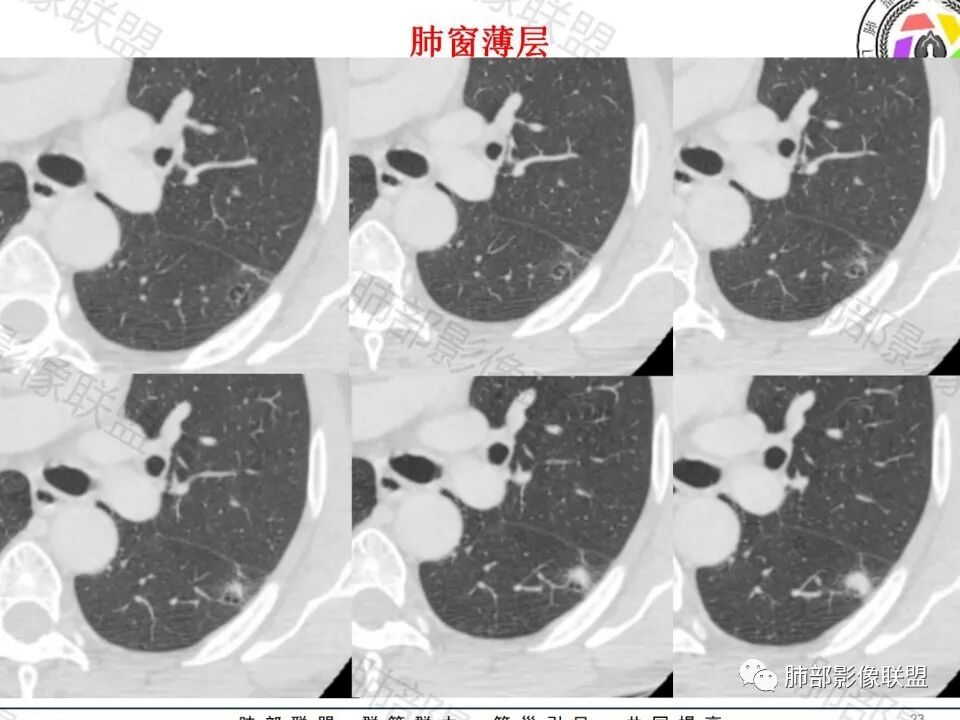

影像:轻微肺气肿,可能抽烟;旁边有个卫星灶4-5个,厚层无血管弯,薄层叶间裂轻度增厚,有囊腔,内侧有一个微血管,弯,另有两个微血管直,膨隆,增强血管不弯,糊墙,好像边界有些模糊,17-47-47,冠位轻度叶间裂弯。

这个囊可靠吗?

这应该是附近的肺气肿

血管进去还是比较自然

类圆形,边缘稍平直,周围晕中细微毛刺,密度均匀,均匀强化,血管走形自然,稍牵拉扭曲,支气管在近端堵塞

多发类似结节